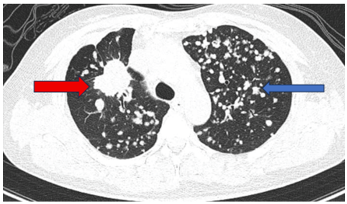

Ca lâm sàng: Điều trị đích bệnh nhân ung thư phổi không tế bào nhỏ giai đoạn muộn di căn nhiều cơ quan, tại Trung tâm Y học hạt nhân và Ung bướu – Bệnh viện Bạch Mai

Ung thư phổi là nguyên nhân hàng đầu gây tử vong do ung thư trên toàn thế giới. Trong đó, ung thư phổi không tế bào nhỏ (NSCLC) là thể thường gặp nhất, chiếm khoảng 85% các trường hợp [1]. Phần lớn...